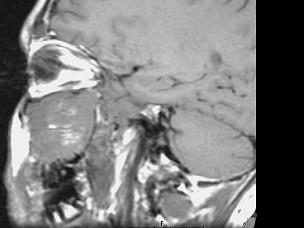

15岁,男性,渐进性鼻塞1年余,MRI扫描如图所示,请选择最可能诊断 ( )

• A.鼻咽部脓肿

• B.鼻咽部纤维血管瘤

• C.脊索瘤

• D.鼻咽癌

• E.鼻咽部囊肿

答案: B